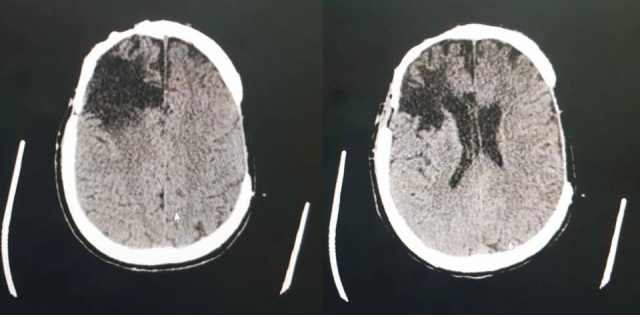

Pulmonary arteriovenous malformations (PAVM) are characterized by abnormal pulmonary vessels forming arteriovenous shunts that compromise oxygenation of the blood, causing hypoxemia, and predispose to infections and cerebral ischemia. The patient in this case was a 38-year-old male who presented with tachypnea and dyspnea, cyanosis of extremities, and significant digital clubbing. The patient had structural epilepsy secondary to neurosurgery for a cerebral abscess during childhood. Arterial blood gas analysis showed significant hypoxemia (PaO2 = 46.2; SaO2 = 77%; PaO2/FiO2 = 70) and a chest computed tomography showed PAVM in the apical segments of the right upper and lower lobes, with ectatic and tortuous vascular structures following an intraparenchymal path, communicating with the pulmonary artery and veins. After confirmation of the PAVM, it was concluded that elevated pulmonary resistance was contributing to refractive hypoxemia and hypercapnia. Gradual reduction of the ventilation parameters, primarily controlled pressure and positive end-expiratory pressure, and consequent reduction of the arteriovenous shunt, resulted in progressive improvement of oxygenation and respiratory mechanics. The vascular surgery team's assessment was that treatment with embolization was warranted.